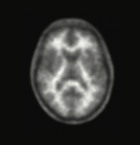

氟[18F]贝他苯是一种18F标记的二苯代乙烯衍生物,能够与大脑皮层中的Aβ斑块特异结合,18F同位素产生正电子信号的可由脑正电子发射断层扫描(PET)扫描,直观地显现出大脑中Aβ斑块的存在与否以及空间分布。

医生会根据氟[18F]贝他苯注射液 PET 扫描结果以及其他检查和观察结果来做出诊断。本品阴性显像结果说明图像采集时大脑中未见或仅有少量β-淀粉样蛋白神经炎性斑块沉积,不符合AD的神经病理学诊断,提示由AD引起的患者认知障碍的可能性较低。阳性显像结果说明大脑中有中度至频繁β-淀粉样蛋白神经炎性斑块沉积。已有的神经病理学检查结果表明,此量级的淀粉样神经炎性斑块可存在于AD患者中,但也可能存在于其他类型的神经系统疾病患者以及认知正常的老年人中。本品可以为评价AD和其他痴呆症提供辅助检测。